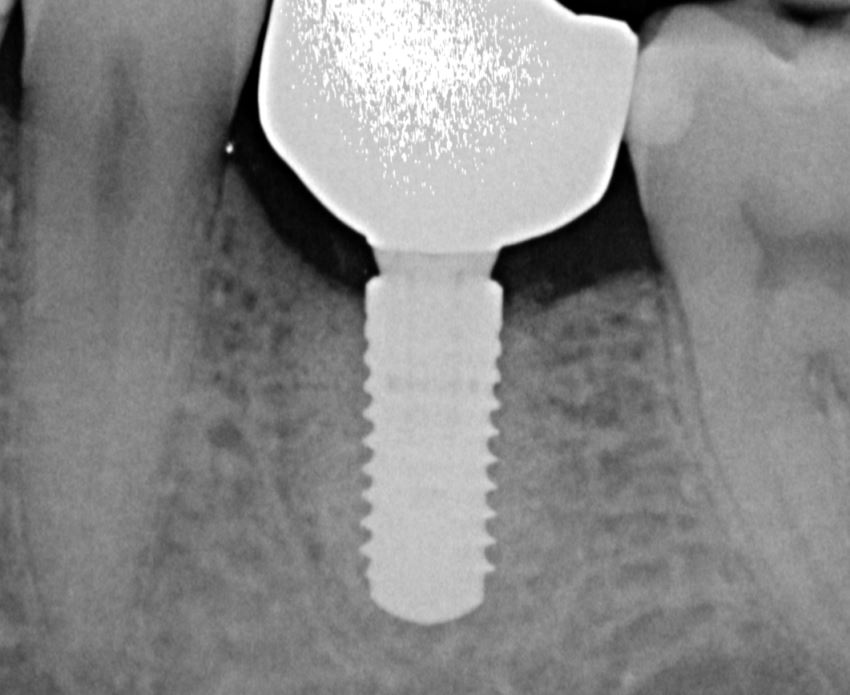

Abb. 2

Zweidimensionale röntgenologische Aufnahme (intraoral) mit Saggitalansicht nach prothetischer Versorgung und des noch erkennbaren periimplantären Augmentationsbereichs.